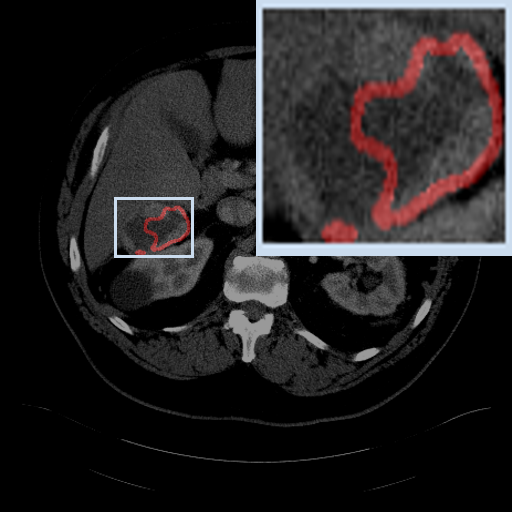

Refer to caption

KiTS21-Case 58

Pancreas-Case 345

LiTS17-Case 76

Colon-Case 141

(a) Image

(b) Ground Truth

(c) Ours

(d) w/o FED

Figure 4: Qualitative analysis visualization of Feature Enhanced Decoder (FED) on four datasets.

IV-C2 Qualitative analysis of Feature Enhanced Decoder

We also perform qualitative analyses on several cases, as illustrated in Fig. 4. The visualizations indicate that removing the original image features leads to a significant inaccuracy in the size of the segmented regions across the four datasets. This outcome underscores the importance of the original image features in accurately capturing the size of the target region. This aligns with our intuition that incorporating the original image information enhances the spatial features, resulting in more precise segmentation in both size and shape.